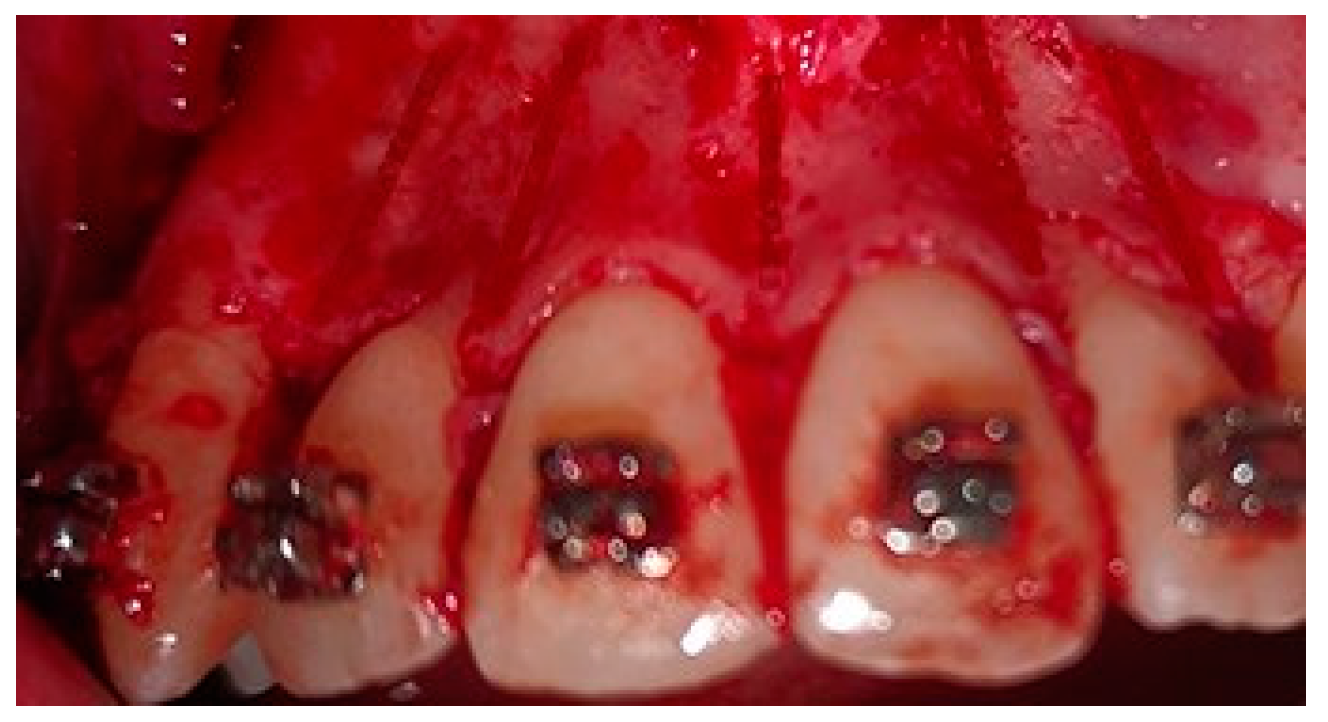

2.5. Surgical Phase